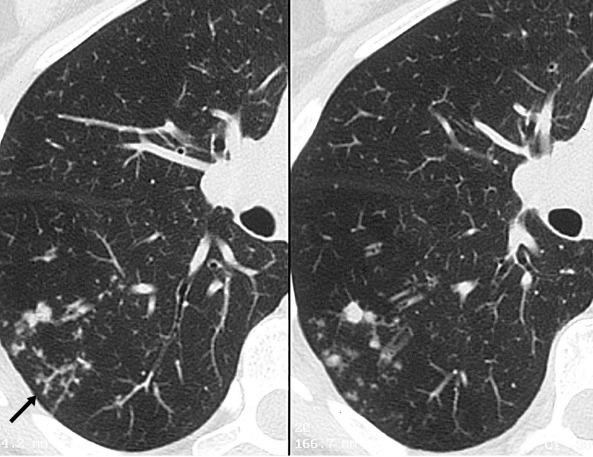

支气管肺炎

症状:发热、咳嗽、气促或呼吸困难,早期为刺激性干咳,后期咳嗽有痰,出现呼吸增快,鼻翼扇动及“三凹症”(吸气时,两锁骨上窝、胸骨上窝出现凹陷)。